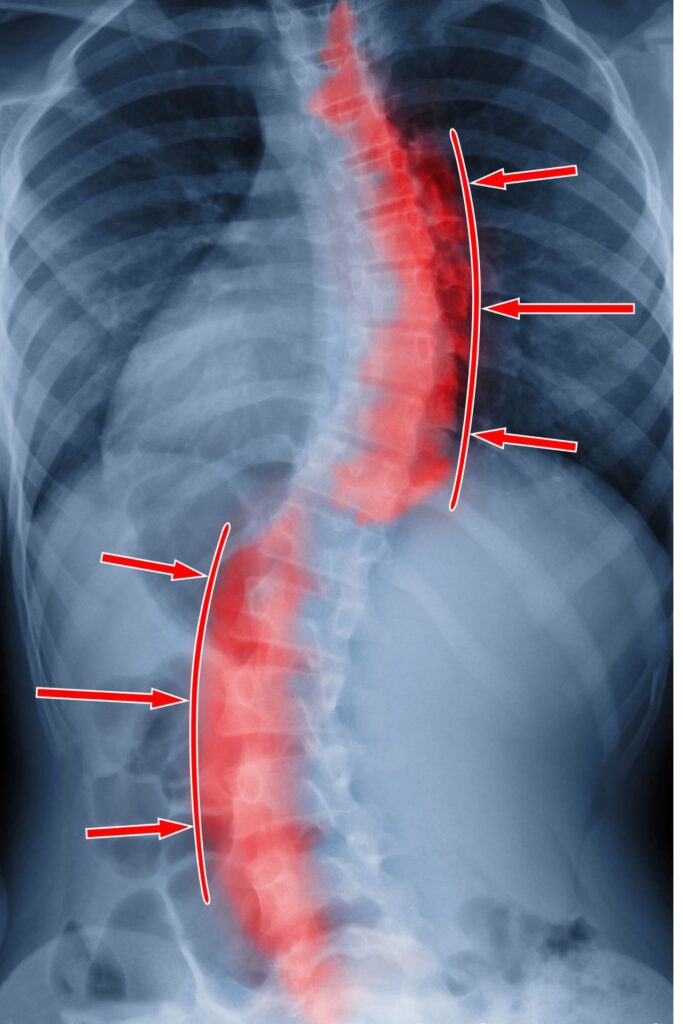

- ma stwierdzoną skoliozę,

Nie musisz mieć badań, na pierwszej wizycie po zbadaniu dziecka ustalimy czy w przypadku Twojego dziecka takie badania są potrzebne. Jeśli posiadacie badania RTG kręgosłupa to przygotuj je na pierwszą wizytę